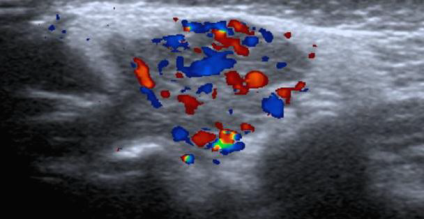

Hlavné diagnostické kritériá

Hlboká podkožná hmota

Hypoechogenic & hypervascularized tumor

Diagnostika hemangiómov a cievnych malformácií

- Sonografické vyšetrenie – MR, MR-angio